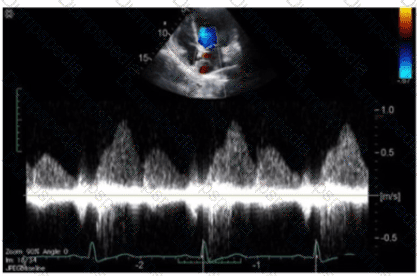

Which Doppler signal is most consistent with significant aortic valve regurgitation?

Which patient positioning is best for obtaining the waveform seen in this image obtained by a non-imaging transducer?